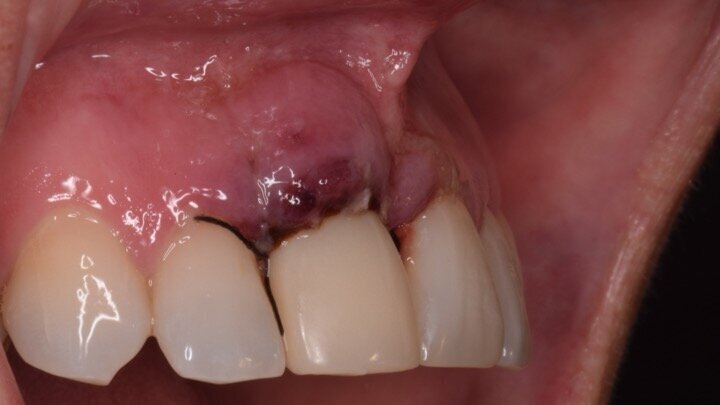

Figura 1. Atrofia de más del 50% de la pared vestibular en el diente 11 con infecciones de repetición de varios años de evolución.

Figura 5. Hundimiento de la zona estética anterior inmediatamente después de la extracción del diente por la reabsorción de la pared vestibular.